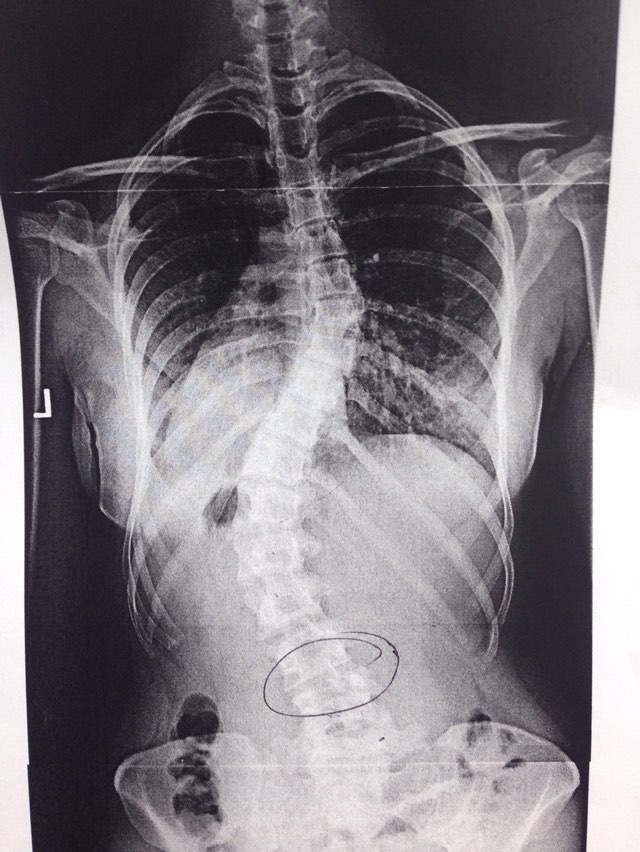

June is Scoliosis awareness month and as many of you know I have pretty severe scoliosis.

For those of you who don’t know scoliosis is defined as an abnormal lateral curvature of the spine.

I first discovered I had scoliosis in high school after I was having lots of back pain. The crazy part is- my scoliosis could have been prevented. In middle school I was on growth hormone because at 14 I had the bone age of a 6 year old. They started me on growth hormone shots but I wasn’t growing at the rate they had expected so eventually we stopped. Years later we discovered I had been growing, just not straight! If they had been more thorough and monitoring my back they would have seen that I was developing scoliosis and put me in a brace at night. Instead here I am- a little extra curvy.

In high school when I was dealing with the back pain we entertained the idea of surgery. It would have been MAJOR. They would insert a huge metal rod along my spine to strengthen it and in the end I decided against it. For insurance purposes it was considered “cosmetic” (crazy right?!) and doctors said it may not even help with my pain so it seemed like a very expensive gamble.